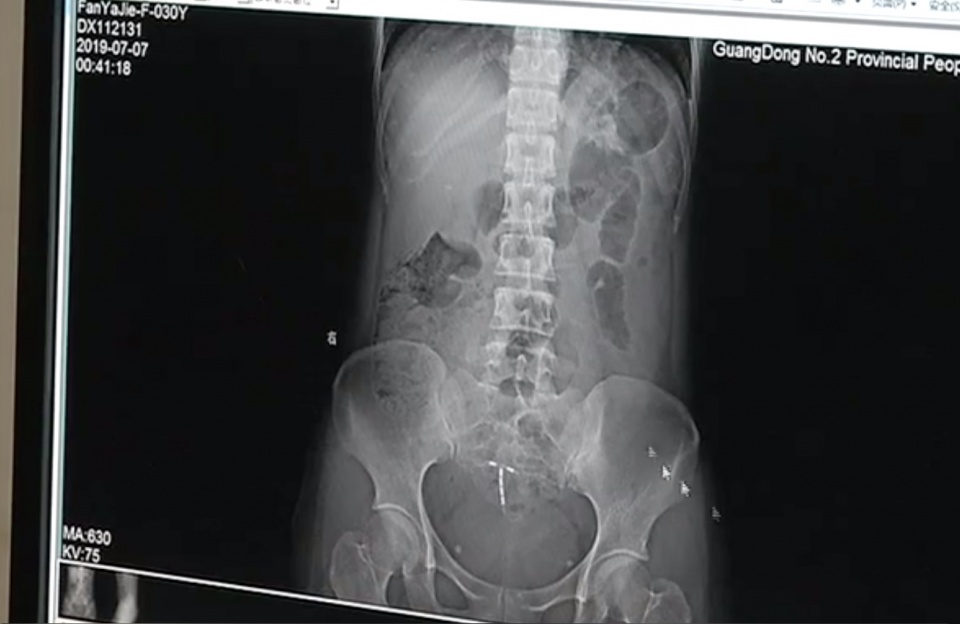

考虑到邢女士受伤的部位比较特殊,医生同时邀请了妇科、泌尿外科、内镜中心一起会诊,当时她截石位6点钟方向自皮肤至肛管大片撕裂,长度大概4厘米。

医生:基本排除泌尿系和生殖系统的问题,后面的治疗基本明确是直肠肛管的损伤,大概在当晚两点钟左右给患者做了一个全麻手术,手术内容是给患者做直肠肛管的清创处理。